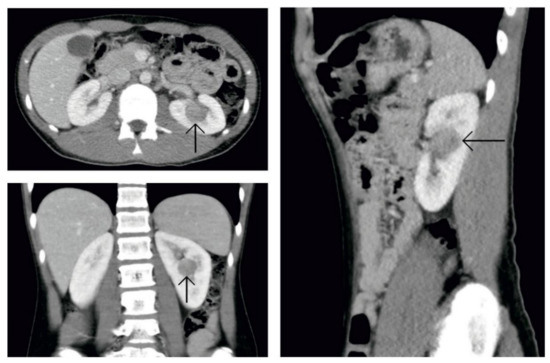

2. Case Presentation